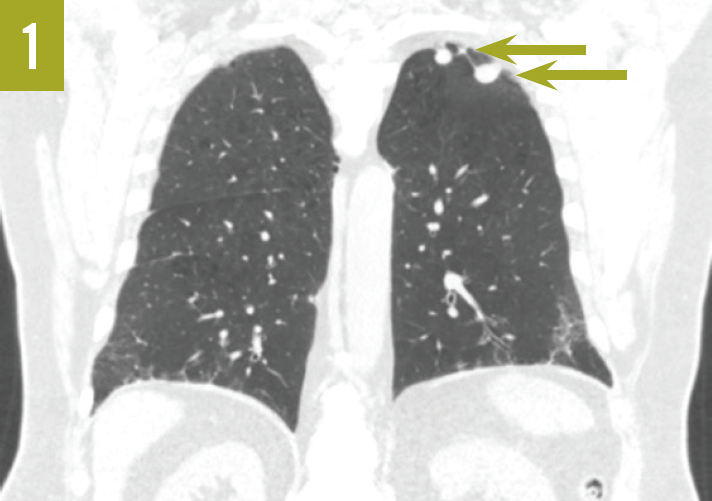

Rheumatoid lung nodules at ct are round or lobulated, several millimeters to several centimeters in size, and often peripheral with mid upper lung predominance. There may be multiple nodules in both lungs. Lung nodules usually cause no signs. Rheumatoid nodules are firm lumps under the skin. They tend to form close to joints in people affected by rheumatoid arthritis. Lungs as a site for the initiation of rheumatoid arthritis (ra). Often called rheumatoid nodules, these benign lumps rarely cause symptoms but occasionally can rupture. These bumps can be as large as a. They are commonly multiple but may manifest as a single nodule. Lung nodules that develop from ra, called pulmonary rheumatoid nodules, are rare.

What Are Rheumatoid Nodules In Lungs Lungs as a site for the initiation of rheumatoid arthritis (ra). Rheumatoid lung nodules at ct are round or lobulated, several millimeters to several centimeters in size, and often peripheral with mid upper lung predominance. Lungs as a site for the initiation of rheumatoid arthritis (ra). Small lumps can form in the lungs (rheumatoid nodules), as well as in other parts of the body. There may be multiple nodules in both lungs. Rheumatoid nodules are firm lumps under the skin. These bumps can be as large as a. They tend to form close to joints in people affected by rheumatoid arthritis. Lung nodules usually cause no signs. Often called rheumatoid nodules, these benign lumps rarely cause symptoms but occasionally can rupture. They are commonly multiple but may manifest as a single nodule. The respiratory system can be less often involved at the upper. Lung nodules that develop from ra, called pulmonary rheumatoid nodules, are rare.